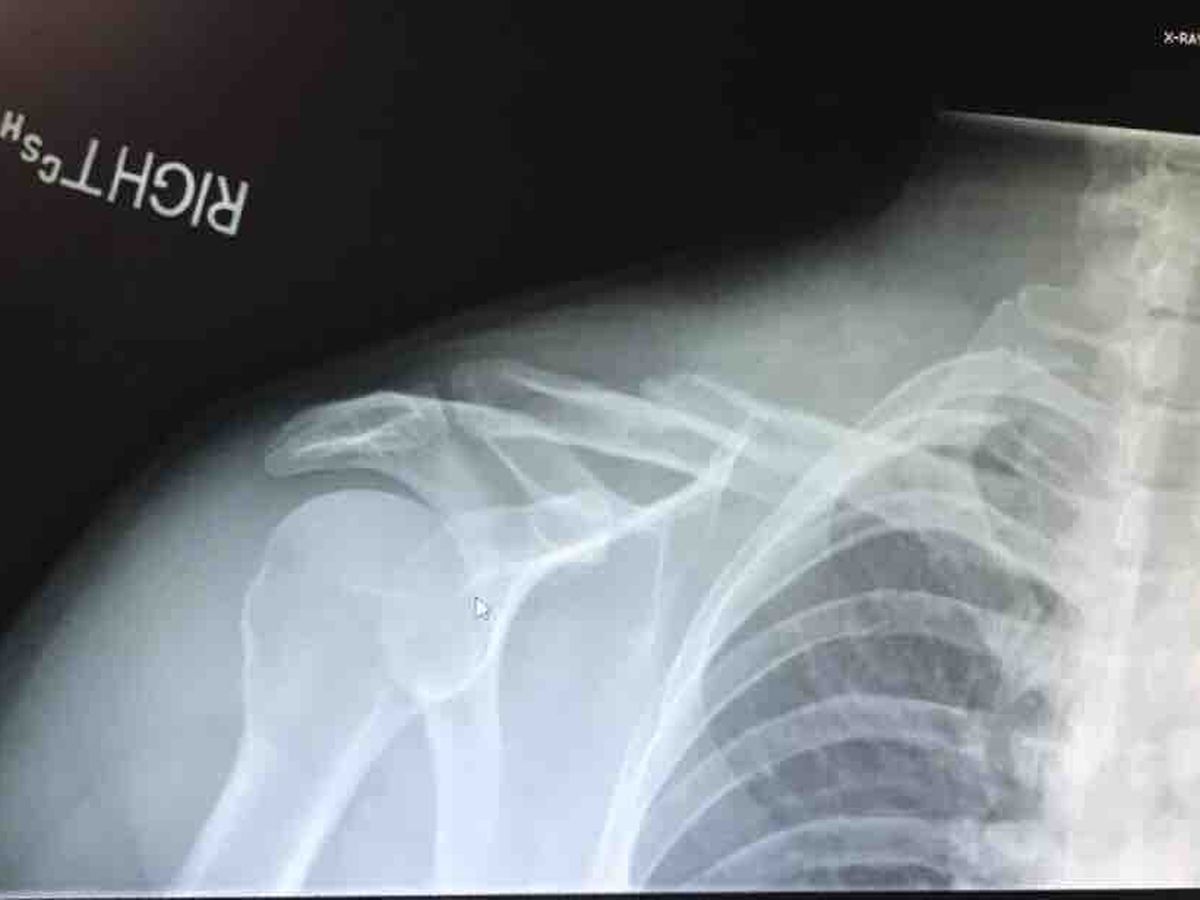

A shattered clavicle and 6 broken ribs.

Two of those ribs broken twice.

They installed a titanium plate and multiple screws where my clavicle was.